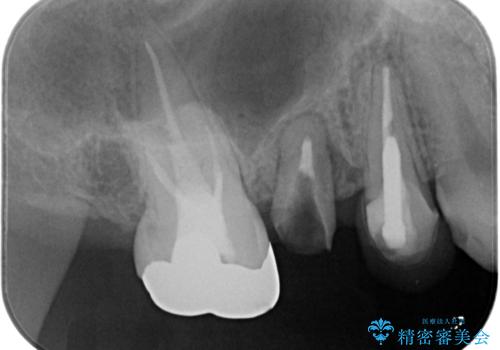

- 「奥歯のクラウンが取れてしまったので診てほしい。」とセラミック治療を希望され来院されました。

診査を行ったところ、クラウンの取れた歯は、割れてしまっており再度クラウン装着が難しい状況でした。

抜歯を行ったのち、ブリッジ製作を行うことで咬合機能の回復を計画します。